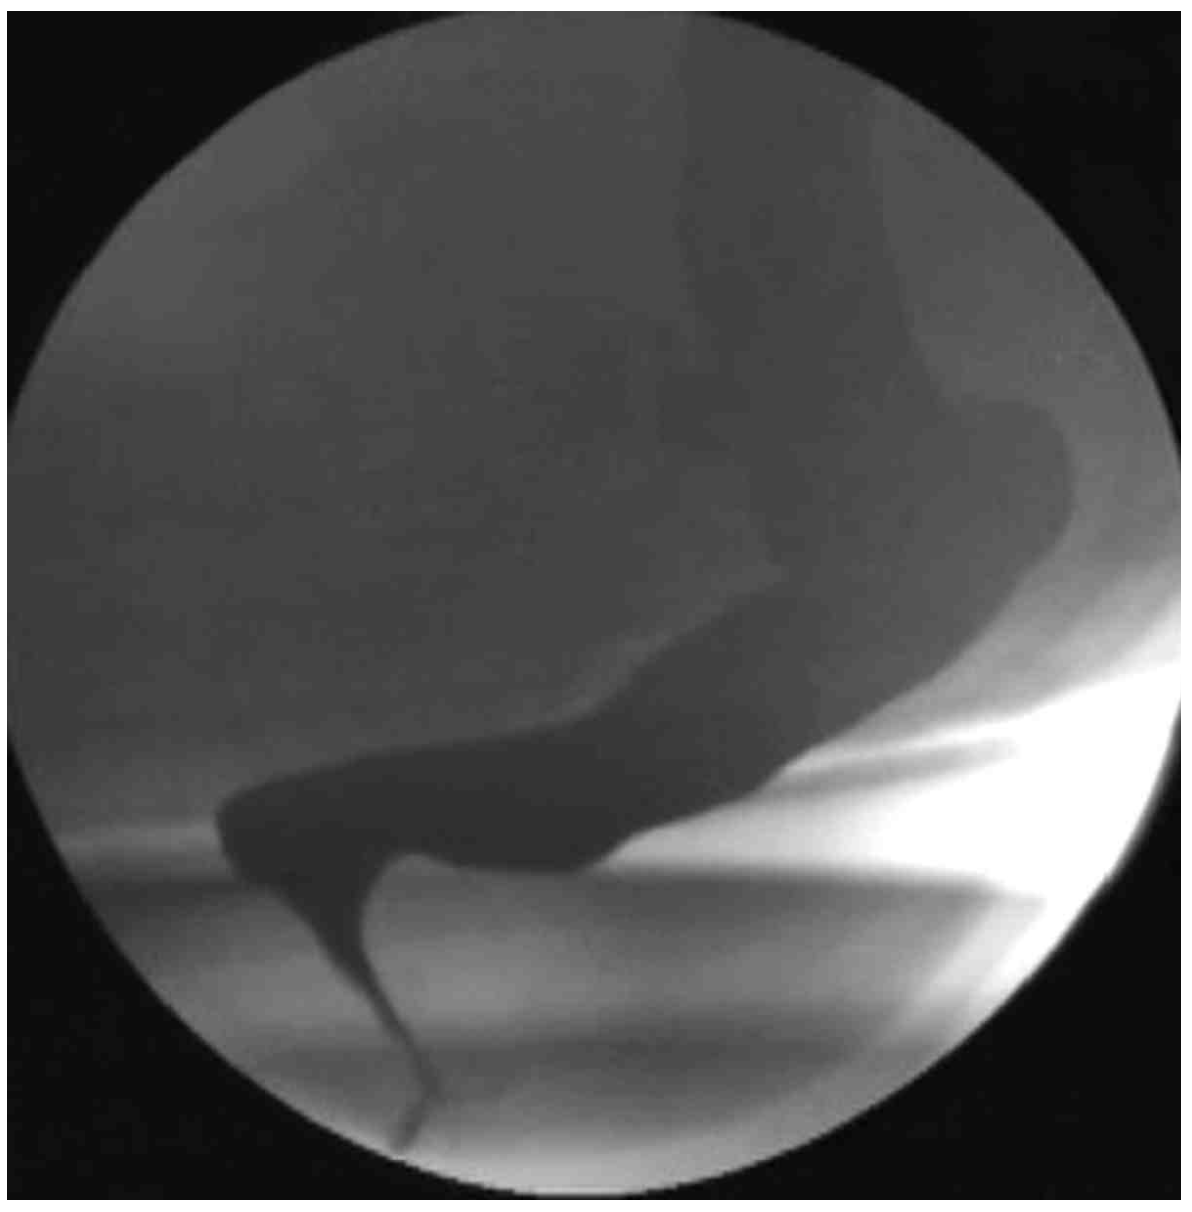

대장통과시간 측정 검사: radiopaque한 표지자들이 직장/항문에 집중적으로 존재

배변조영술: Severe angulation of rectum by pelvic floor muscles

• 대장통과시간 검사 결과 radiopaque한 표지자들이 직장/항문 주위에서 집중적으로 관찰되는데, 이는 골반저 기능장애를 시사하는 소견이다.

• 배변조영술에서는 anorectal angle이 정상 각도에 비해 다소 작게 관찰되는데, 이 또한 골반저 기능장애를 시사하는 소견이다.

• 배변조영술(defecography)로 골반저기능장애를 평가하려면 평상시의 사진과 환자가 배변을 위해 힘을 줄 때의 사진이 같이 주어져야 한다. 힘을 줄 때 정상적인 경우라면 anorectal angle이 증가해야 하지만, 골반저기능장애 환자의 경우 pelvic mucle의 discoordination으로 인해 anorectal angle에 변화가 없거나, 오히려 각이 감소하는 경우가 있다. 본 증례에서는 사진이 한 개만 주어졌고, 해당 사진이 평상시에 찍은 것인지 힘을 줄 때 찍은 것인지에 대한 부연 설명이 없으므로 배변조영술로만 골반저기능장애를 진단하기에는 다소 무리가 있다.